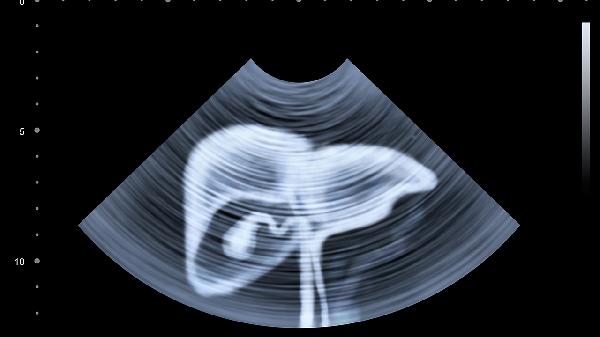

病毒感染引起的肠系膜淋巴结肿大是儿童腹痛常见原因,疼痛多位于脐周或左下腹,可能伴有低热。超声检查可确诊。家长需让孩子充分休息,发热时配合物理降温,医生可能开具蒲地蓝消炎口服液、小儿豉翘清热颗粒等中成药辅助治疗。